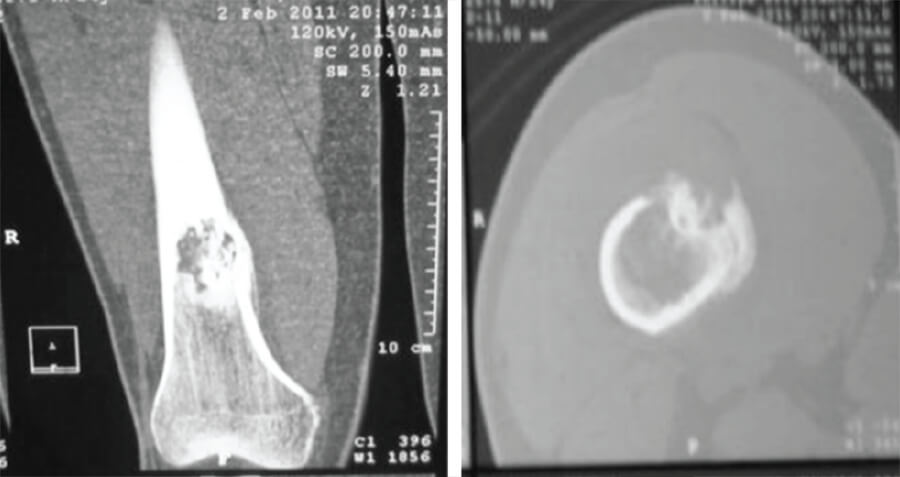

Los estudios de laboratorio reportaron LDH= 110 UI/ L y fosfatasa alcalina= 95 UI/L, encontrándose dentro de los valores de referencia. Se realizó TC del fémur distal que evidenció “lesión episifisiometafisiaria del tercio distal del fémur de aproximadamente 4 x 5 cm, con gran reacción perióstica, irregularidades y destrucción de la cortical e invasión de tejidos blandos vecinos” (Fig. 2). El GMO reportó “incremento de la captación en el tercio distal del fémur derecho”. Se realizó una biopsia incisional (Hospital Universitario de Los Andes, número 78-10) de la lesión que reportó “hallazgos histopatológicos compatibles con osteosarcoma”. Se estableció el diagnóstico de osteosarcoma de fémur, estadío III.

Figura 2. TC al en sus cortes coronal (izquierda) y axial (derecha).